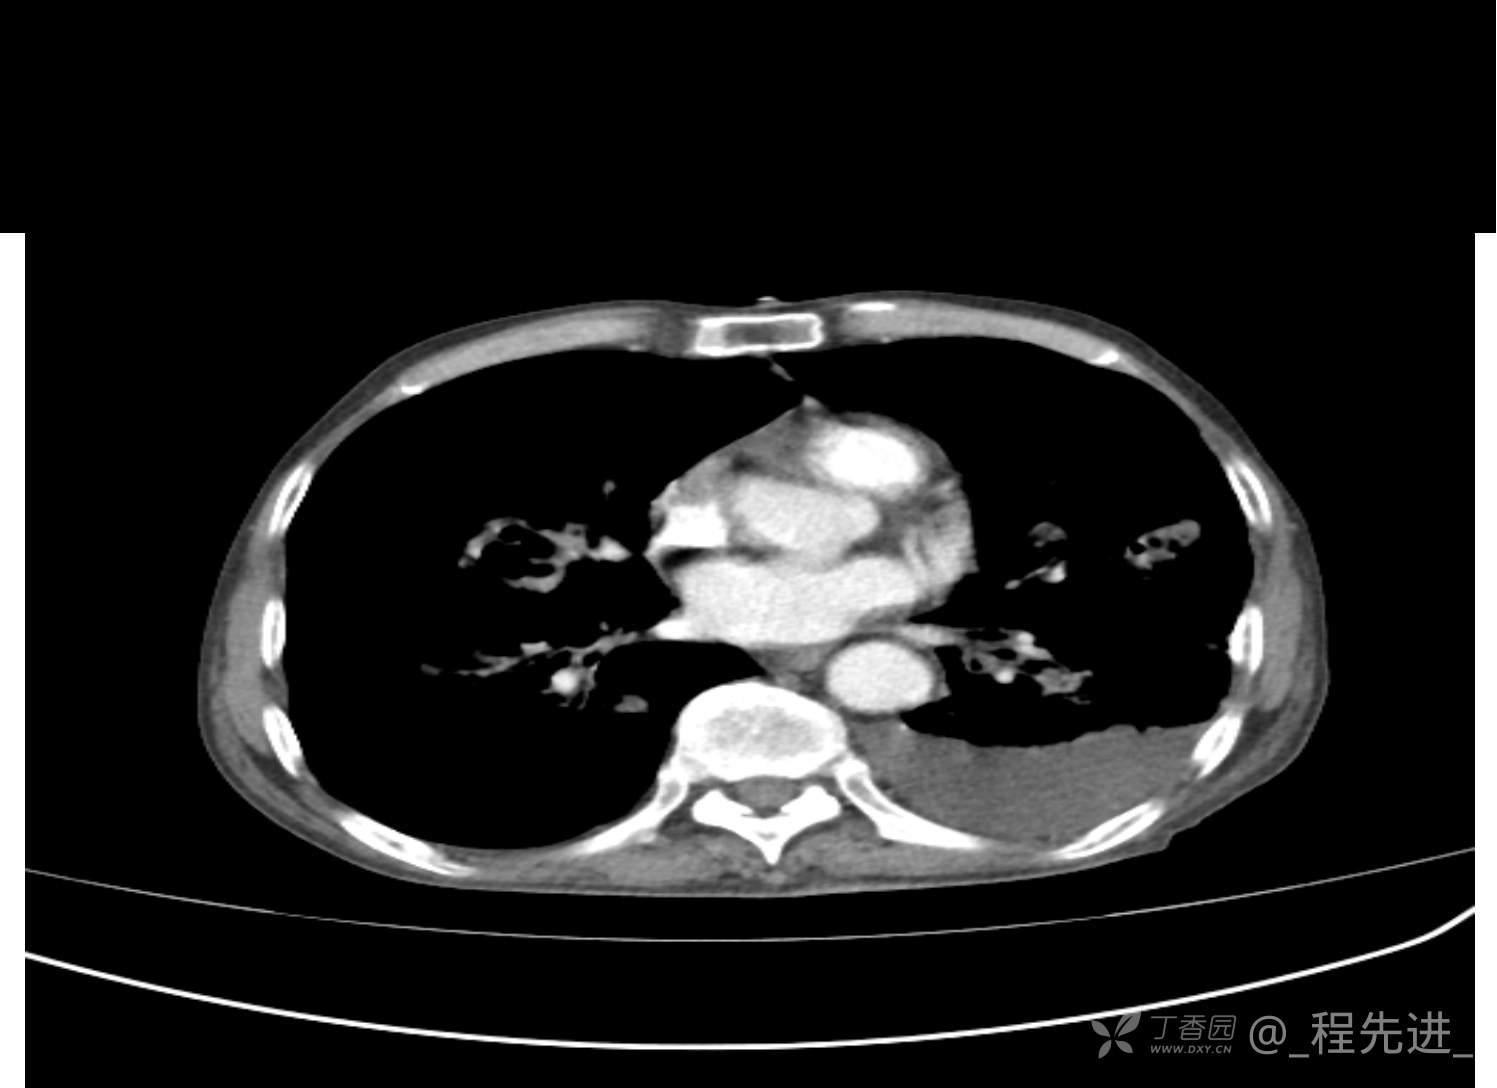

患者性别:男

患者年龄:81岁

简要病史:反复咳嗽、咳痰20余年,加重1周。两肺呼吸音低,可闻及散在干湿啰音。